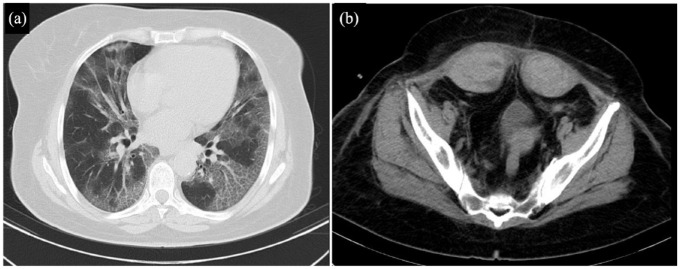

The COVID-19 pandemic has had an enormous impact on the healthcare systems. Along with its common complications, novel complications such as Rectus Sheath Hematoma (RSH) have been reported. We present 2 cases of RSH. (A) A 63-year-old woman with a known case of COVID-19 with severe cough presented sudden tachycardia and hypogastric pain; on physical examination, a huge lower abdominal tender mass was noticed. All the differential diagnoses were ruled out. (B) A 57-year-old woman with COVID-19 started complaining of tachycardia, pain, and a mass in the lower abdomen. On the physical examination, a lower abdominal tender mass was noticed. Both of the patients underwent an abdomen CT scan which confirmed a huge RSH. Conservative treatment and cessation of anticoagulant medications were continued. Both of them recovered and no evidence of further expansion was seen after 4 weeks of follow-up.